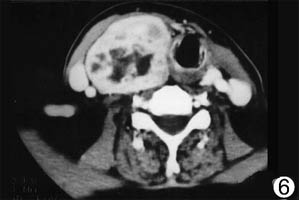

2.CT掃描 胸部及腹部CT,有助於了解有無縱隔、腹腔內外的淋巴組織病變。

2.輔助檢查 血常規、骨髓穿刺、全身骨掃描等可排除血液疾病;細針穿刺抽吸細胞學檢查(FNAC)、活組織病理檢查可明確診斷;X線檢查、CT掃描、B超等,有助於發現轉移病灶。